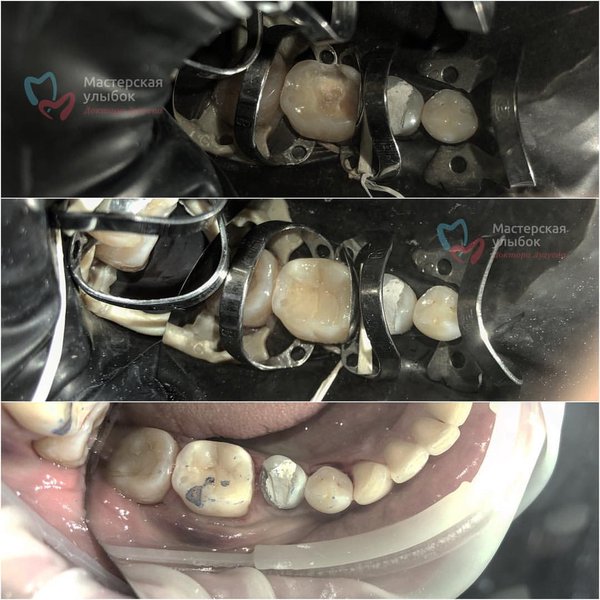

Люблю лечение по сегментам! Сразу все анестезировали, изолировали,вылечили и можно радоваться жизни . Работа врача: Лугуева Арслана. . Запись по тел.: ️ #